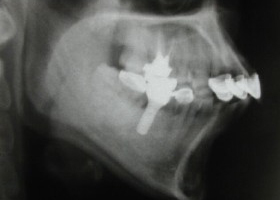

1.術前口內正面照、局部X光片。

proimages/case/cosmetic/pic_case-020.jpg

proimages/case/cosmetic/pic_case-021.jpg